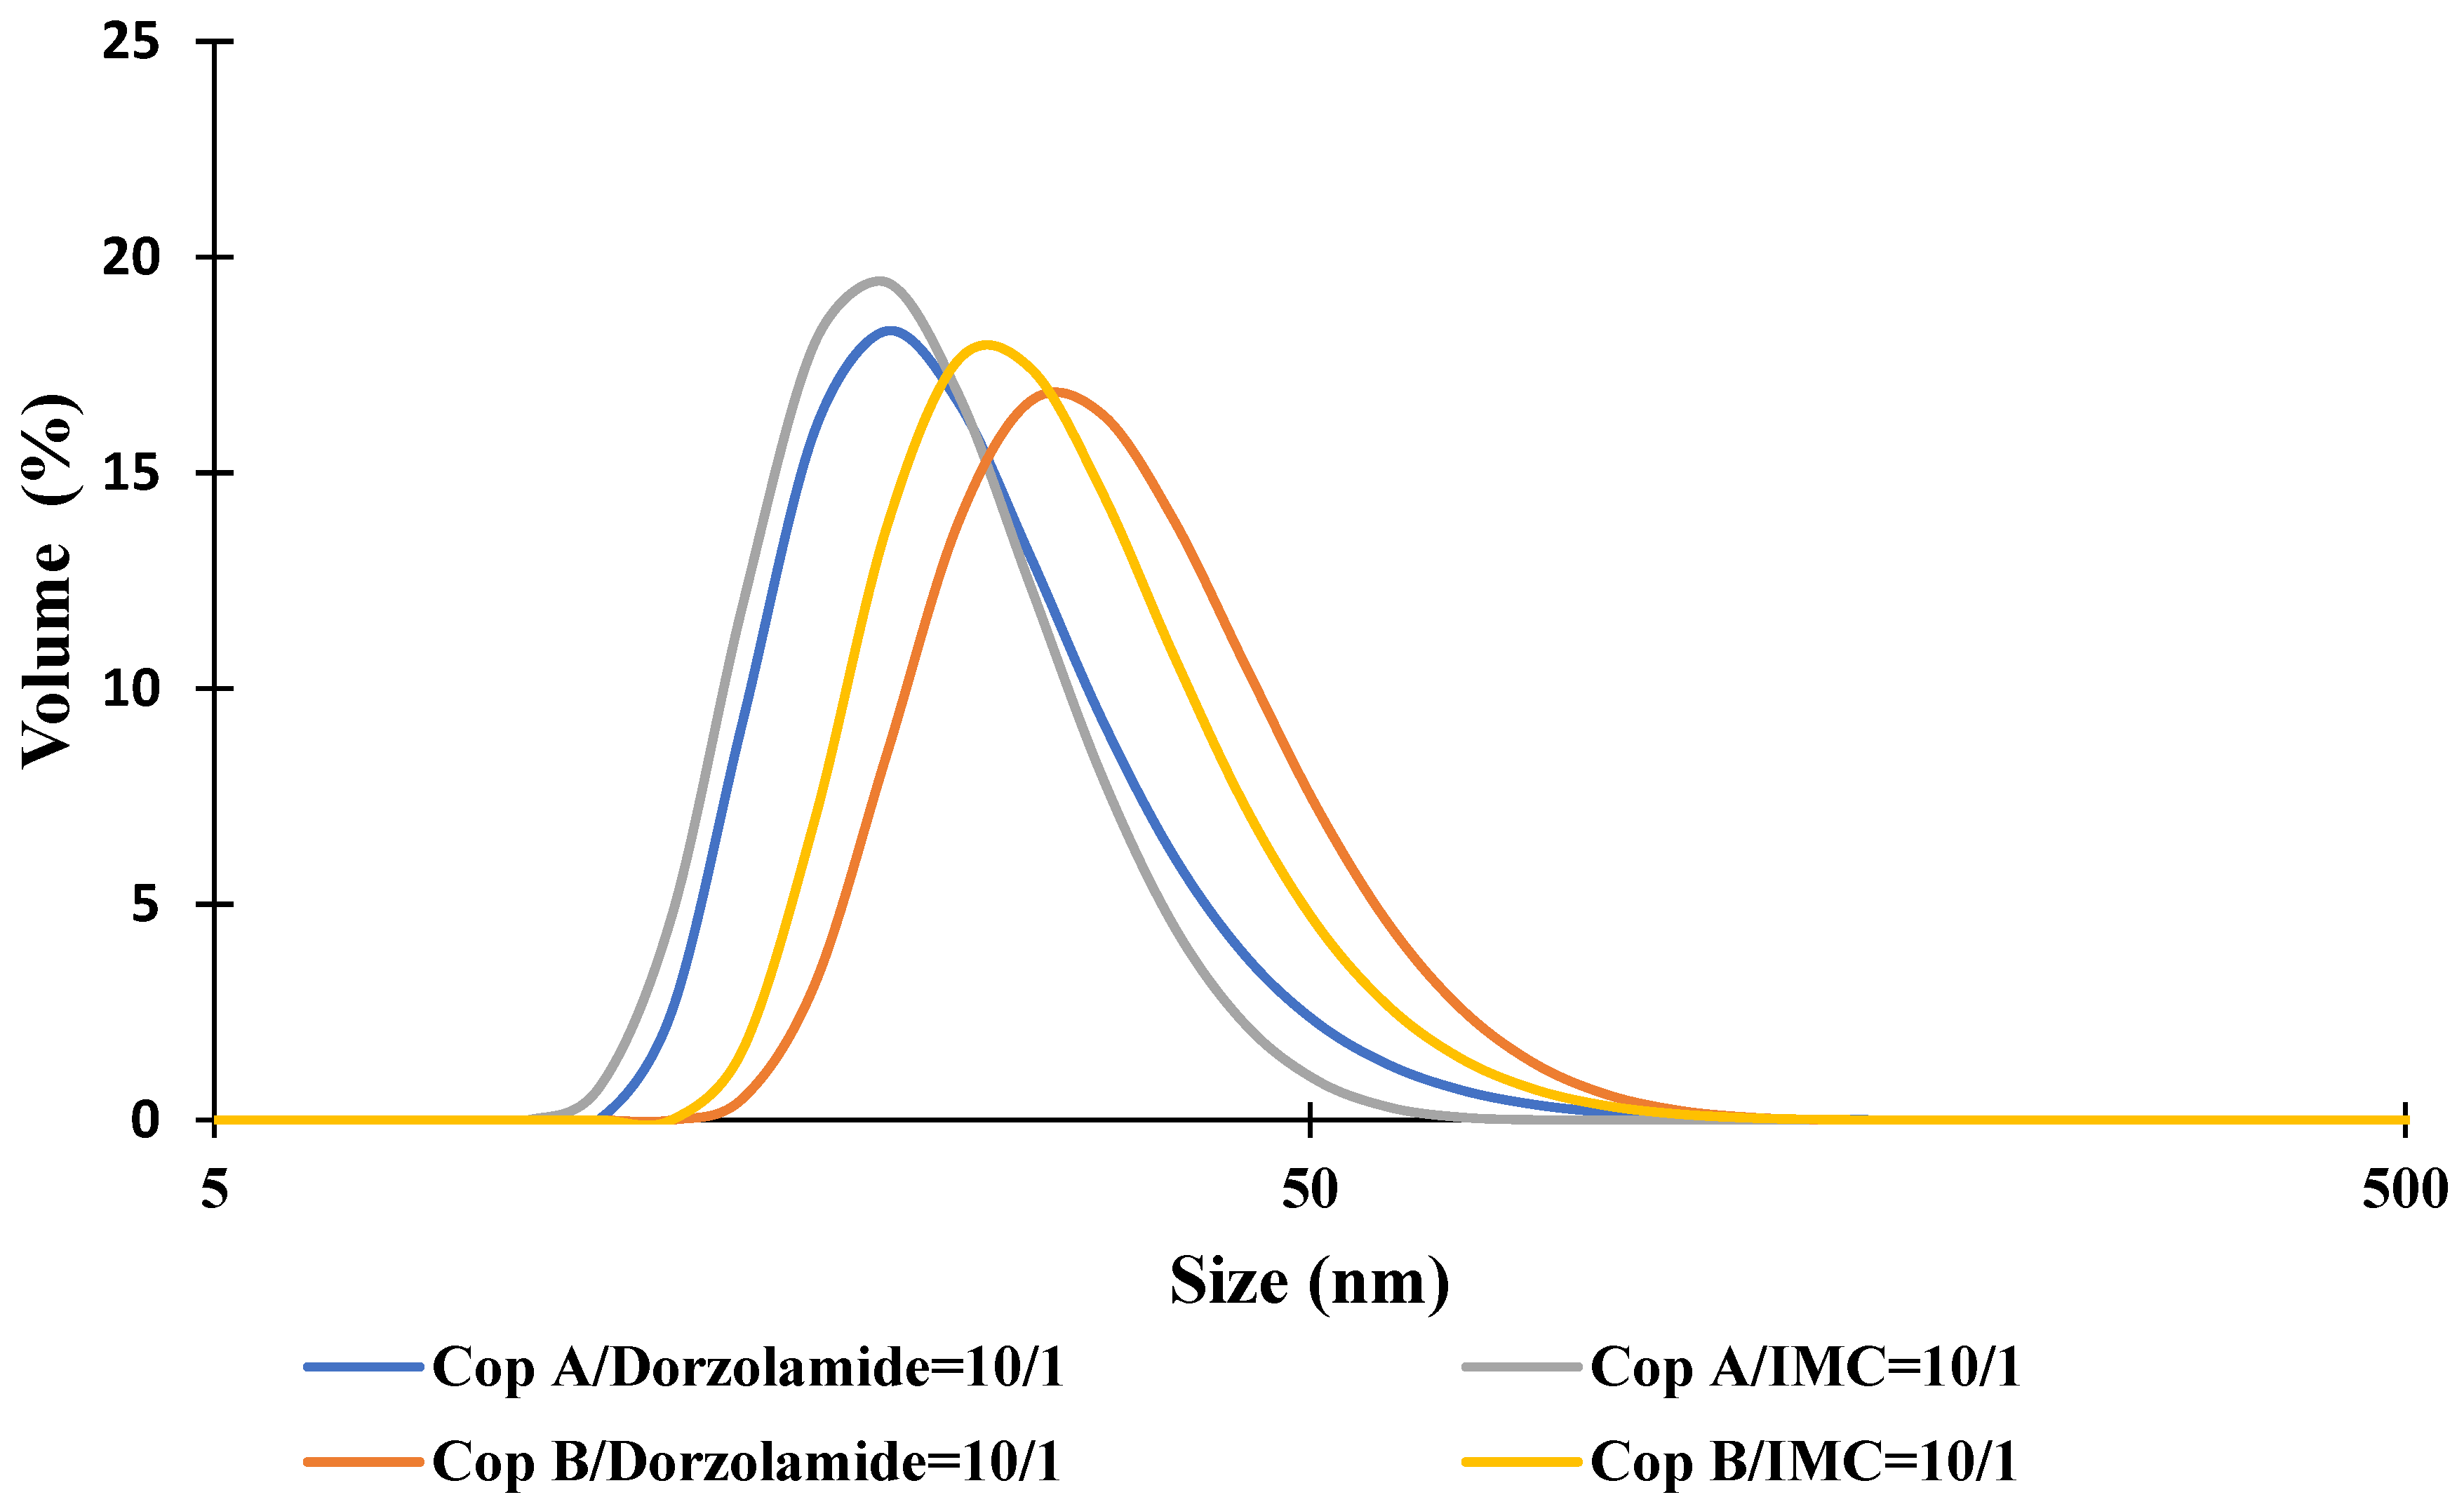

2.1. Micellar Sizes and Stability

| Sample | Z-Average (nm) | Dv (nm) | PDI | ZP (mV) | DEE (%) | DLE (%) |

|---|---|---|---|---|---|---|

| Cop A | 39.4 ± 0.1 | 24.2 ± 0.2 | 0.197 | −3.5 | - | - |

| Cop A/Dorzolamide = 10/1 (wt/wt) | 41.3 ± 0.4 | 24.5 ± 0.5 | 0.258 | −3.3 | 20.2 | 4.4 |

| Cop A/IMC = 10/1 (wt/wt) | 29.6 ± 0.3 | 23.0 ± 0.1 | 0.154 | −7.5 | 68.5 | 6.3 |

| Cop B | 47.2 ± 0.2 | 34.8 ± 0.4 | 0.200 | −3.3 | - | - |

| Cop B/Dorzolamide = 10/1 (wt/wt) | 54.8 ± 0.3 | 37.5 ± 0.2 | 0.354 | −3.3 | 34.0 | 6.7 |

| Cop B/IMC = 10/1 (wt/wt) | 41.8 ± 0.4 | 31.0 ± 0.1 | 0.161 | −5.5 | 75.1 | 8.2 |

| Cop B/Dorzolamide = 10/1+Cop B/IMC = 10/1 (50/50 wt/wt) | 45.7 ± 0.5 | 33.9 ± 0.2 | 0.252 | −4.1 | - | - |